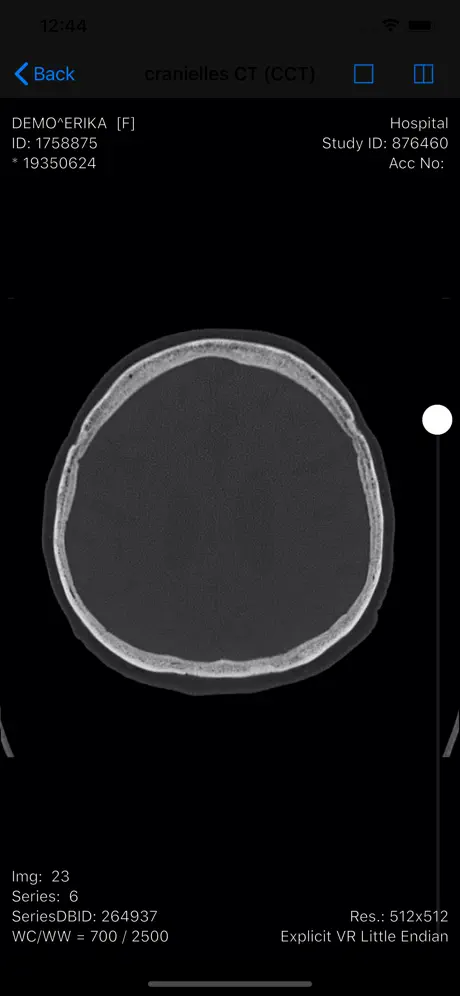

Die RVC Mobile App ist eine native iOS Applikation welche sicher

mit dem einheitlichen RVC Server kommuniziert. Mit dieser App werden iPAD, iPod touch und iPhone zu mobilen Clients die Inhalte aus RVC Clinical PACS / mDMAS intuitiv anzeigen. Dadurch ist ein ortsunabhängiger Zugriff auf das multimediale Archiv möglich. Als Mehrwert dieser Clients wurde auch eine Foto- und Videodokumentation mit integriert, sodass Fotos oder auch Videos direkt vom mobilen Endgerät in das Archiv gespeichert werden können.

- Anzeige von DICOM Objekten

- Anzeige von DICOM Objekten

Screenshots